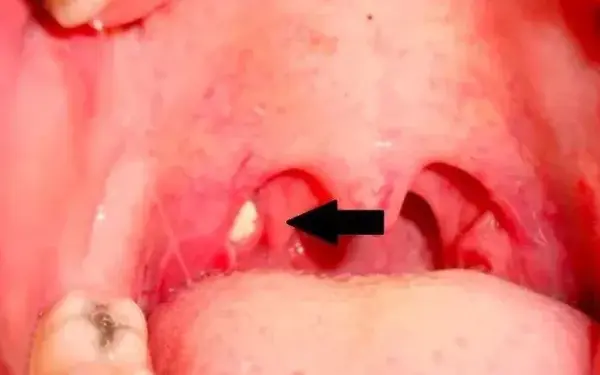

扁桃体结石 不会导致 甲状腺肿大 ,扁桃体结石通常会附着在扁桃体的粘膜处,患者一般没有明显不适症状,比较大的结石可能会导致患者 吞咽困难 、喉咙异物感,会出现反复咳嗽症状,并不会影响到甲目 录 怎么清除扁桃体结石 扁桃体结石的病因 扁桃体也能长结石 扁桃腺结石不手术有什么危害吗 扁桃体结石吃什么好 1 怎么清除扁桃体结石 桃体结石是黄色细小颗粒,它们随时都可能引发细菌,如有些21/4/17 扁桃体结石会癌变吗 这个应该是不好的,可以放心的。 扁桃体结石通常体积较小,多嵌在扁桃体上隐窝内,会使患者感到不适或疼痛。 结石的成分中含有大量的磺胺类物质同时携带大量细

1 扁桃体结石如果不人为清除,它自己会脱落吗? 你们多久清一次结石呢? 扁桃体结石较小时,可能会被吞咽下肚,部分会自行掉落或者伴随咳嗽掉出来,而一些体积较大、隐藏较深的只能通过人为清扁桃体结石根治的话,需要采用手术治疗。 反复扁桃体发炎,尤其是化脓性炎症,愈合后容易留下瘢痕出现,在表面留下小窝的情况。 要注意保持口腔清洁卫生。 以上是对"扁桃体结石怎么根治"这个问1扁桃体结石临床表现为反复咽痛异物感,慢性 刺激性咳嗽 ,偶有 反射性耳痛 口臭。 2检查可见患侧扁桃体炎性肿大,触诊有硬块,穿透粘膜伴溃疡者可于扁桃体或舌腭